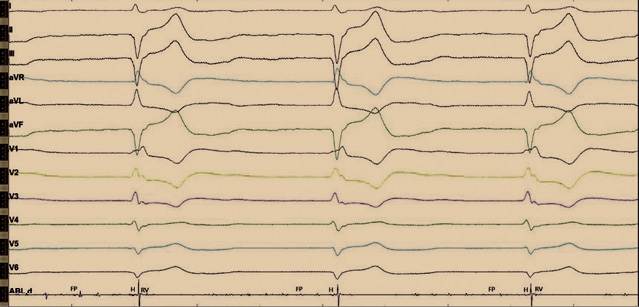

Согласно данным эхокардиографического исследования при поступлении у пациента наблюдалось расширение всех полостей сердца. Фракция выброса – 51%. Гипокинезия – сегменты 1, 7, 6, 12, 5. Отмечался склероз аорты, расширение корня и восходящего отдела. Митральная недостаточность 2-й степени – S рег. На программировании перед операцией ЭКС находился в режиме VVI(R), с базовой частотой сердечных сокращений 65 в минуту (рис. 1). Импеданс желудочкового электрода 646 Ом, чувствительность желудочкового электрода – 15,2 мВ. Порог стимуляции по желудочковому каналу 0,7 В. Срок службы составил 5 месяцев.

Рис. 1. Электрокардиограмма до операции. Постоянная желудочковая стимуляция в однокамерном режиме VVI(R) с базовой частотой 65 ударов в минуту. Длительность QRS 180 мс

Рис. 2. Интраоперационное изображение с электрофизиологического монитора во время отключения электрокардиостимулятора. Отмечается нарушение внутрижелудочкового проведения по типу блокады правой ножки пучка Гиса и блокады передней ветви левой ножки пучка Гиса. Регистрируются эндограммы c аблационного катетера: фибрилляции предсердий (FP), проводящей системы (H) и высокоамплитудные желудочковые эндограммы (RV). На данном рисунке эндограммы H и FP трудно различимы между собой, однако стимуляция с картирующего электрода данной области позволяла получить стимуляционный комплекс, идентичный с нативным. Более выраженную эндограмму пучка Гиса зафиксировать не удалось. Предположительно, это связано с ранее проведенной аблацией атриовентрикулярного соединения

Рис. 4. Электрокардиограмма после операции. Отражена постоянная желудочковая стимуляция после имплантации гисиального электрода. Стимуляционный комплекс не расширен, соответствует нативному. Определяются стимуляционный спайк, изолиния и сокращение желудочков. Имеется также второй страхующий стимул, после которого нет ответа, по типу псевдосливного комплекса. Изолиния отражает замедление проведения по специализированным клеткам проводящей системы, с последующим сокращением по системе Гиса – Пуркинье. Длительность QRS составляет 110 мс

Стимуляция проводящей системы сердца позволяет реализовать физиологическую стимуляцию у пациентов с нарушением предсердно-желудочкового проведения, что и было показано нами на данном клиническом примере. Выполненное оперативное вмешательство позволило снизить длительность комплекса QRS со 180 до 110 мс. Несмотря на блокаду ножек пучка Гиса, стимулированный комплекс имел длительность нативного. Высокий порог гисиального электрода обосновывает применение второго желудочкового электрода с целью страхующей стимуляции. На наш взгляд, использование страхующей стимуляции не только оправдано в связи с возможным ростом порога стимуляции в раннем и отдаленном послеоперационном периодах, но и служит гарантией при дислокации электрода. На высокий порог стимуляции может влиять установка электрода не с первой попытки – при неоднократных попытках манипуляций и вкручиваний в миокард ухудшаются физические качества спирали электрода.